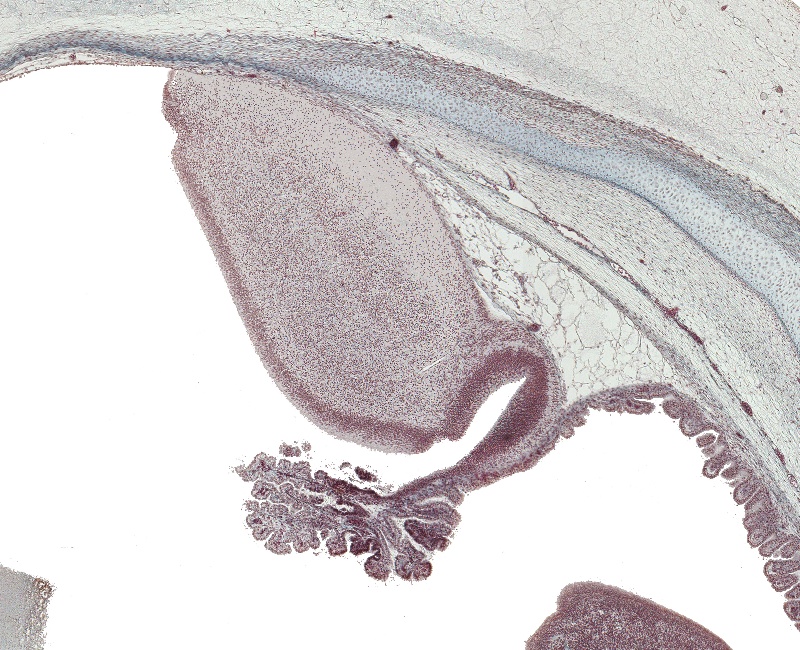

Tissue

–

Medulla Oblongata

Carnegie Embryo #9226

Location:

37-01-01